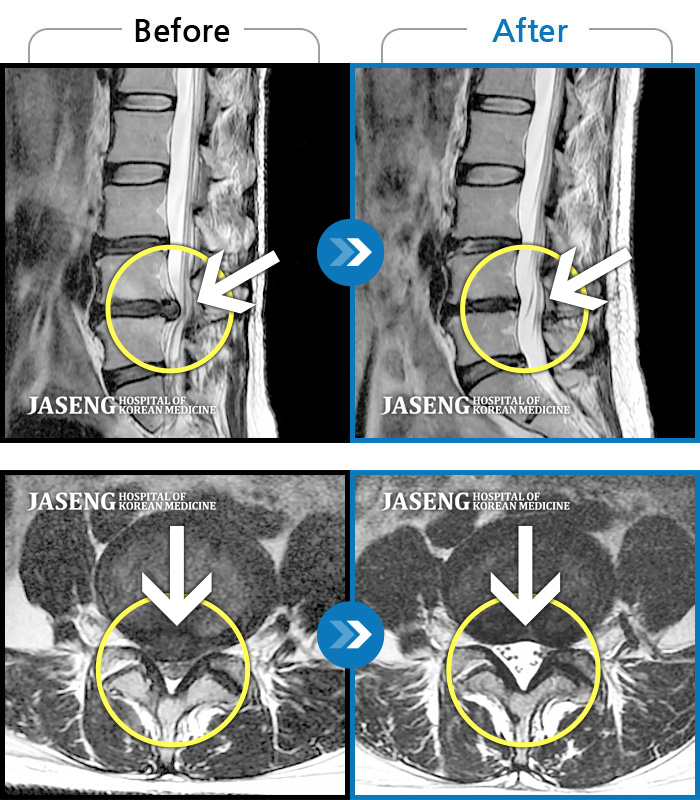

MRI 치료사례

우측 허리 다리 통증으로 야간통, 보행장애